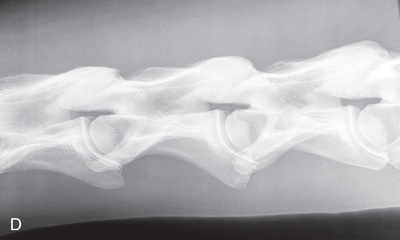

| Thoracic spine | Lateral (Fig. 24.59) | Side of the patient on area of interest. | Opposite side. | Area of interest perpendicular to the image receptor. | Often completed for the dorsal spinous processes (withers). |